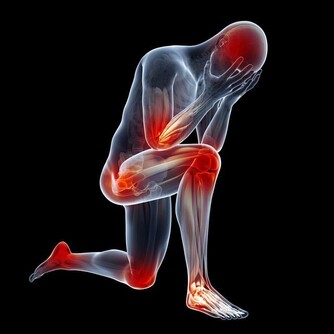

如果我們吃下去,很可能會出現急性中毒,發燒、腹痛、嘔吐、厭食等身體上的不適至少得折磨我們三五天,

嚴重的甚至會在幾個月後發生中毒性肝病表現,

黃疸、肝臟腫大、肝區疼痛、脾大、腹水、下肢浮腫及肝功能異常,

還可能出現心臟擴大、肺水腫,甚至痙攣、昏迷等症狀。